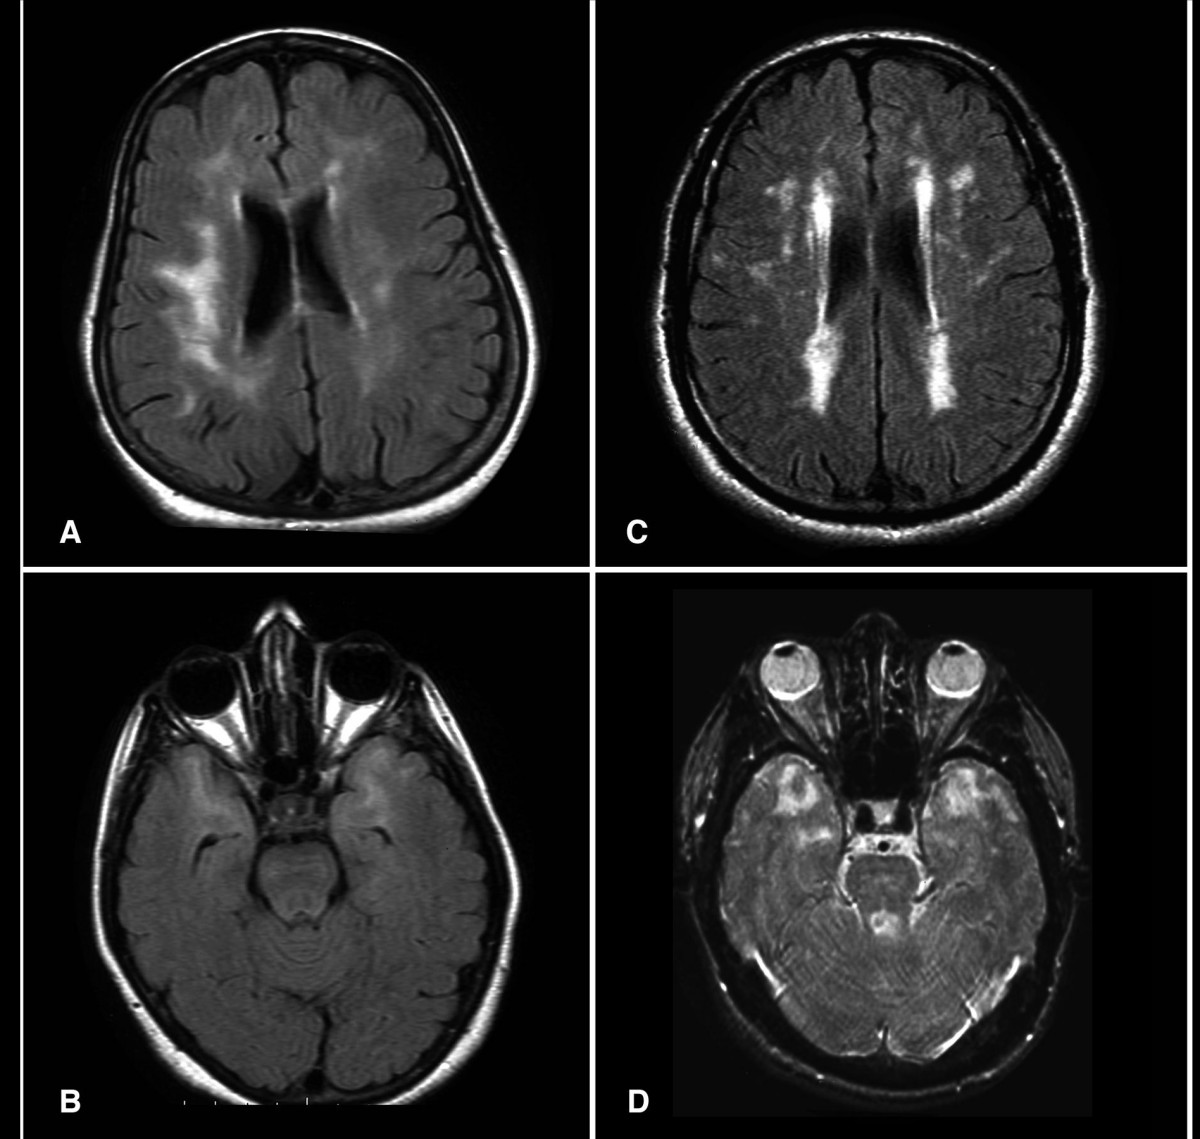

Normal Brain Mri Vs Dementia

Inflammation tied to brain changes in those with dementia.

Normal brain mri vs dementia. Vascular dementia is a decline in thinking skills caused by conditions that block or reduce blood flow to the brain depriving brain cells of vital oxygen and nutrients. Normal pressure hydrocephalus nph refers to a condition of pathologically enlarged ventricular size with normal opening pressures on lumbar puncture. First thing to know. How to tell the difference between dementia vs.